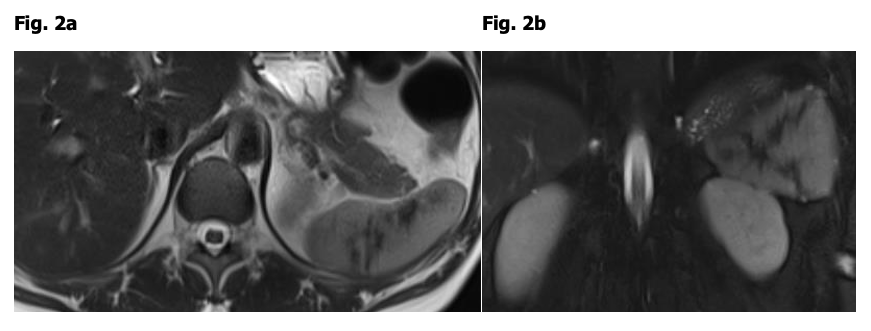

Figure 2: 42 y/o woman, currently without symptoms

a) a) Transverse T2.

b) b) Coronal T2 SPAIR show hypointense intralienal streaks.

Diagnosis: old contained intralienal rupture after severe, prolonged coughing

If we talk to a patient without current symptoms with T2 hypointense intralienal streaks and learn that there was no previous surgery or trauma but that she had suffered from a long period of severe cough years ago with a hitherto unexplained attack of severe left upper quadrant pain, we can decode her findings as contained intralienal rupture during coughing and avoid further follow-up (Fig. 2).